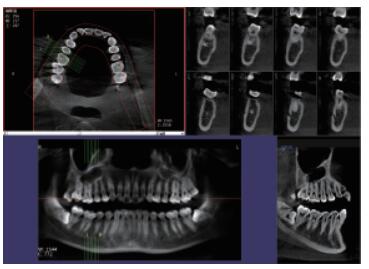

4、口腔CBCT(口腔CT)

CT相對(duì)其他牙片來(lái)講,不管是功能還是設(shè)備上都是比較高級(jí)的,醫(yī)生可在電腦上進(jìn)行模擬種植360°的旋轉(zhuǎn)查看口腔狀況,不遺漏任何一個(gè)角落,主要用于根管治療前、阻生牙、根尖囊腫、種植牙、正畸等。

口腔CBCT三維影像